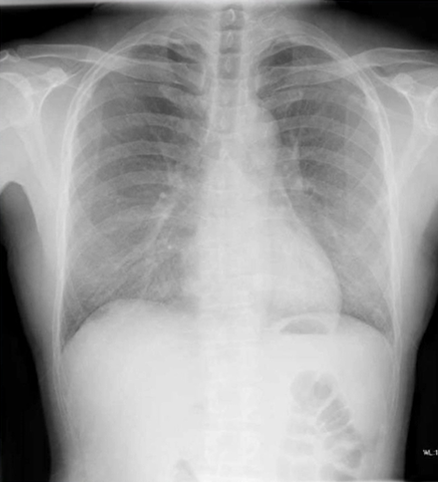

42歳男性。2ヵ月前から左の睾丸が肥大し始めたため泌尿器科外来を受診した。 発熱や寝汗、体重減少、呼吸器症状、尿道分泌物の症状はいずれも認めなかった。 身体所見…